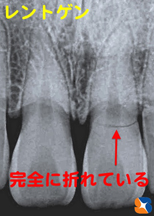

事故で前歯が脱臼グラグラ

カテゴリ:審美 歯科全般

20代の女性。

主訴は「自転車で転倒。前歯がグラグラして今にも抜けそう。風が当っても痛い。見た目も悪いので仮歯が欲しい」。

事故発生から3日後、遠方より来院。

搬送先の病院では、「前歯3本の抜歯」を告げられ、最終的には「6連結のブリッジか、インプラント治療になる」と説明されたそうです。

Dr「あまり期待しすぎないで下さいね」と前置きしたうえで、可能な限り「歯を抜かず、残して修復する」を目標に治療を始めました。 続きを読む